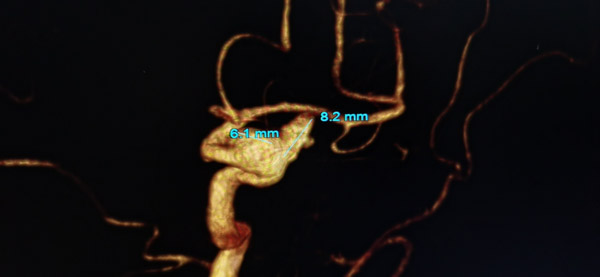

近日,一位63歲女性患者嚴某因體位性眩暈4日后來我院神經外科治療,經DSA檢查后,發現右側頸內動脈床突上段巨大動脈瘤,這顆深藏于顱內的不定時“炸彈”,讓患者感到不安。

確定手術方案后,由吳剛副主任醫師主刀對患者進行血流導向裝置置入+彈簧圈栓塞術治療,經精確測量,選擇了一枚與載瘤動脈匹配良好的血流導向裝置,手術中裝置一次到位并且順利釋放。術中造影復查發現病變頸動脈內血流受血流導向裝置引導基本恢復正常流徑,整個手術過程十分順利,患者獲得了理想的血管重建。